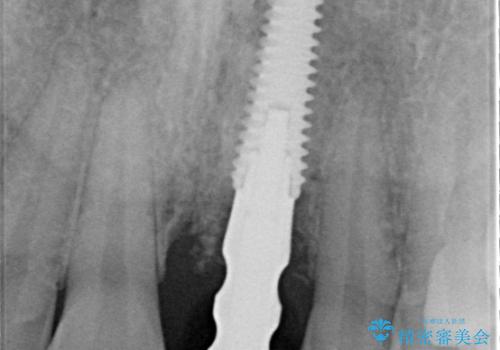

- 歯頚部外部吸収により抜歯適応の歯を抜歯して即時にインプラントを埋入したケースです。

インプラントの手術は二回になることが多いですが、1Dayインプラントの場合は手術は一回で済みます。